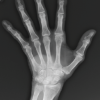

A 23-year-old male patient presented to our institute in November 2016 with discharging sinus in the right axilla for 6 months. He had an alleged history of fall from bike in February 2016 after which he sustained a right pectoralis major muscle avulsion from its humeral attachment. Open repair was done with FiberWire® and endo buttons. In June 2016 (4 months after primary surgery), he developed discharging sinus from axillary region. Discharge was purulent scanty, intermittent, and non-foul smelling. There was no history of fever, weight loss, pain, or restriction of movements. Infection persisted in spite of empirical antibiotics. The wound was not surgically debrided before presentation. He presented to us 5 months after developing the sinus. There was a well healed scar of the previous surgery, with a small sinus over anterior axillary fold in the superior part of the scar (Fig. 1). Discharge was seropurulent and non-foul smelling. There was no tenderness, erythema, or other signs of inflammation around the sinus. Range of motion of shoulder joint was normal and free. Radiographs showed intramedullar endo buttons in the proximal humerus (Fig. 2). MRI of the right chest wall with sinography revealed marginal pus collection in the axillaryregion measuring 3.2 × 2.0 × 1.2 cm with minimal medial extension into pectoralis major and minor muscles along the superior aspect. Three sinus tracts leading from this collection were found converging into axillary discharging sinus at marker site (Fig. 3).